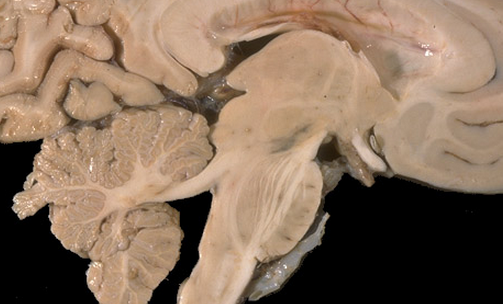

Nuclei in the midbrain

the periaqeudctal gray surrounds the ____

cerebral aqeduct